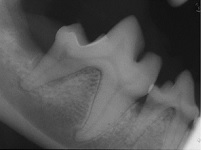

You decide to upgrade your dental suite to incorporate the making of dental radiographs.  The first image you do is that of a dog with periodontal disease of its right mandibular molar tooth.

a. Which radiographic view was used to make this image?

b. Identify the following anatomical structures: enamel, dentin, periodontal ligament space, lamina dura of the alveolar bone, cemento-enamel junction, rootcanal system, mandibular canal and mandibular cortical bone (ventral cortex).

c. Identify the following pathology: vertical bone resorption, horizontal bone resorption, loss of periodontal ligament space.

a. An intra-oral parallel view.  The film is inserted into the dogs mouth and pushed ventrally into the intermandibular space, with the film facing the mandible.  The radiographic beam is at a perpendicular angle to the film and the tooth.  This is the only place in the dog’s mouth where a true parallel technique can be used.